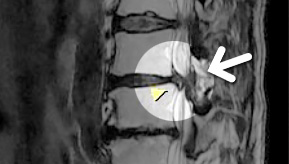

MRI ġ

MRI